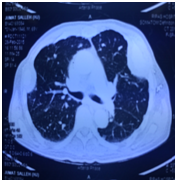

A 60 years old gentleman was referred to us in February 2015 with acute retention of urine. He was admitted to another hospital 5 days ago with the same problem he was treated with catheterization and failed trial without catheter after 3 days with alpha- blockers. Clinically he was cachectic and had a large, hard and non-tender swelling over his left lower jaw as shown in Figure 1 & Figure 2. There were no palpable cervical lymph nodes. Abdominal and Neurological examinations were unremarkable. Digital rectal examination revealed an enlarged T4 prostate cancer. Prostate Specific Antigen (PSA) was 100ng/ml. CT of Mandible showed a large destructive lytic lesion mass over the body of mandible reaching both buccal and lingual cortices and less pronounced lucency within the mandibular body with breech of buccal surface (Figure 3). CT chest showed sclerotic metastases throughout bony cavity with multiple pulmonary metastases (Figure 4). CT abdomen showed a markedly enlarged prostate gland (Figure 5) with secondary hypertrophy of the bladder wall, bilateral iliac lymphadenopathy measuring up to 3 cm and diffuses sclerotic metastases throughout the bony skeleton. Other solid organs are unremarkable.

Figure 4 CT chest showing sclerotic metastases.